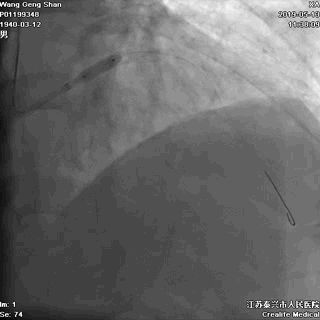

05 LM-LAD支架植入

右头位定位

蜘蛛位定位

LCX球囊拘禁,主支支架释放

回撤LCX球囊